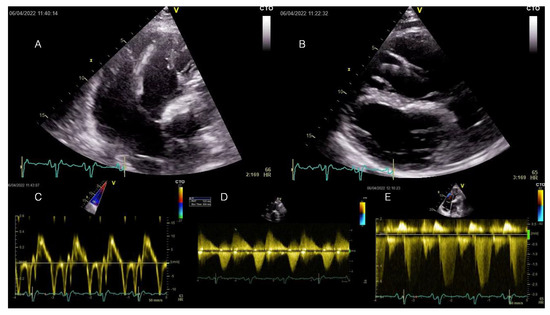

Complex Substrate Leading to PVC-Mediated Systolic Dysfunction in addition to Sustained Monomorphic VT in Repaired Tetralogy of Fallot

Frequent premature ventricular complexes (PVCs) are associated with deleterious effects on left ventricular (LV) function in various clinical scenarios. Repaired tetralogy of Fallot (rTOF) is frequently affected by sustained ventricular arrhythmias dependent on complex post-surgical substrates. However, there is limited data regarding the [...] Read more.

Frequent premature ventricular complexes (PVCs) are associated with deleterious effects on left ventricular (LV) function in various clinical scenarios. Repaired tetralogy of Fallot (rTOF) is frequently affected by sustained ventricular arrhythmias dependent on complex post-surgical substrates. However, there is limited data regarding the potential of arrhythmogenic isthmuses to generate frequent PVCs and PVC-mediated LV systolic dysfunction development in rTOF. We present a case of rTOF experiencing relatively infrequent episodes of internal shocks for episodes of sustained monomorphic ventricular tachycardia and a high burden of PVCs associated with left ventricular systolic function deterioration, in which the successful substrate ablation of the anatomical VT isthmuses also led to PVC abolition and consequently to LV systolic function normalization. In such cases, understanding the pathogenic mechanisms that lead to LV dysfunction is only possible by rigorous clinical reasoning, which leads to a tailored specific treatment. Full article